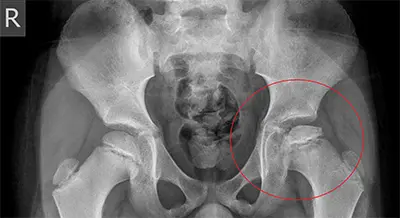

Perthes disease, also called Legg-Calvé-Perthes disease, is a condition that affects the development of the hip in children ages 3 to 12. It occurs when blood flow to the femoral head (the ball of the hip) is disrupted, leading to abnormal growth and shape of the femoral head and hip socket (acetabulum). Boys are four to five times more likely to develop this condition than girls. If left untreated, Perthes disease can lead to early-onset arthritis, pain, and hip dysfunction. While the exact cause is unknown, trauma, circulation issues, and genetics may contribute to the condition.

Diagnosis of Perthes Disease

Because hip pain in children can have multiple causes, diagnosing Perthes disease involves a combination of medical history, physical examination, and imaging tests. Common diagnostic tools include:

- X-rays: Identifies bone deformities or stress fractures.